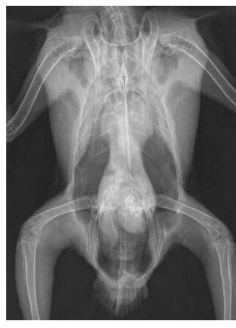

What species radiographs are these and how do they compare to rabbits

guinea pigs

vast majority of body is still abdomen, very small areas for thorax. Shared amongst hind fermenters